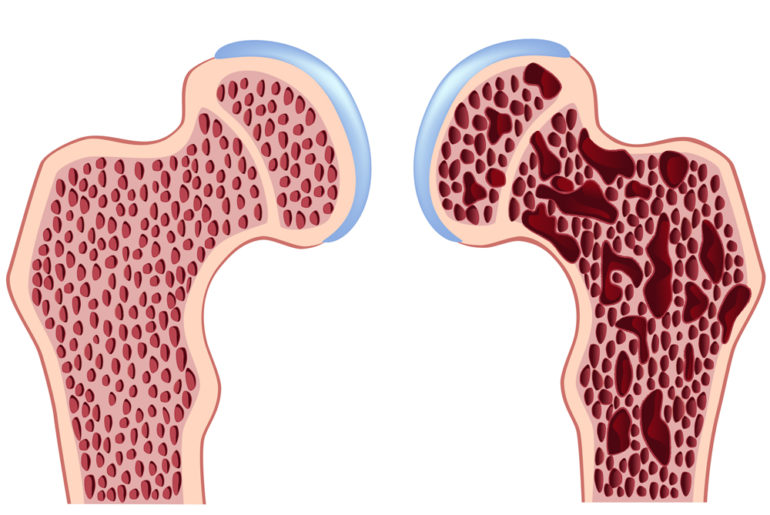

Τη δυνατότητα φαρμακευτικής αγωγής για την οστεοπόρωση, με μία μόνο εβδομαδιαία δόση αντί για καθημερινή χορήγηση, έχουν τώρα και οι Έλληνες ασθενείς. Μελέτες του εξωτερικού έδειξαν ότι, η συμμόρφωση των ασθενών που λαμβάνουν μακροχρόνια θεραπευτική αγωγή για τη νόσο είναι πολύ καλύτερη όταν λαμβάνουν την αγωγή μόνο μία φορά την εβδομάδα και όχι καθημερινά. Όπως ανέφερε ο κ. Σωκράτης Παπαπούλος, καθηγητής Παθολογίας και Διευθυντής του Τμήματος Μεταβολισμού Οστών του Ιατρικού Κέντρου του Πανεπιστημίου Λέϊντεν της Ολλανδίας, στο Πανελλήνιο Ορθοπεδικό Συνέδριο στη Θεσσαλονίκη, οι μελέτες έδειξαν ότι κατά 90% οι ασθενείς έδειξαν σαφή προτίμηση στην εβδομαδιαία αγωγή. Στη χώρα μας εγκρίθηκε πρόσφατα η κυκλοφορία του διφοσφωνικού alendronate sodium (Fosamax) σε εβδομαδιαία δόση, η οποία ισοδυναμεί θεραπευτικά με τη καθημερινή χορήγηση της ίδιας ουσίας. Πηγή: www.iatrikionline.gr